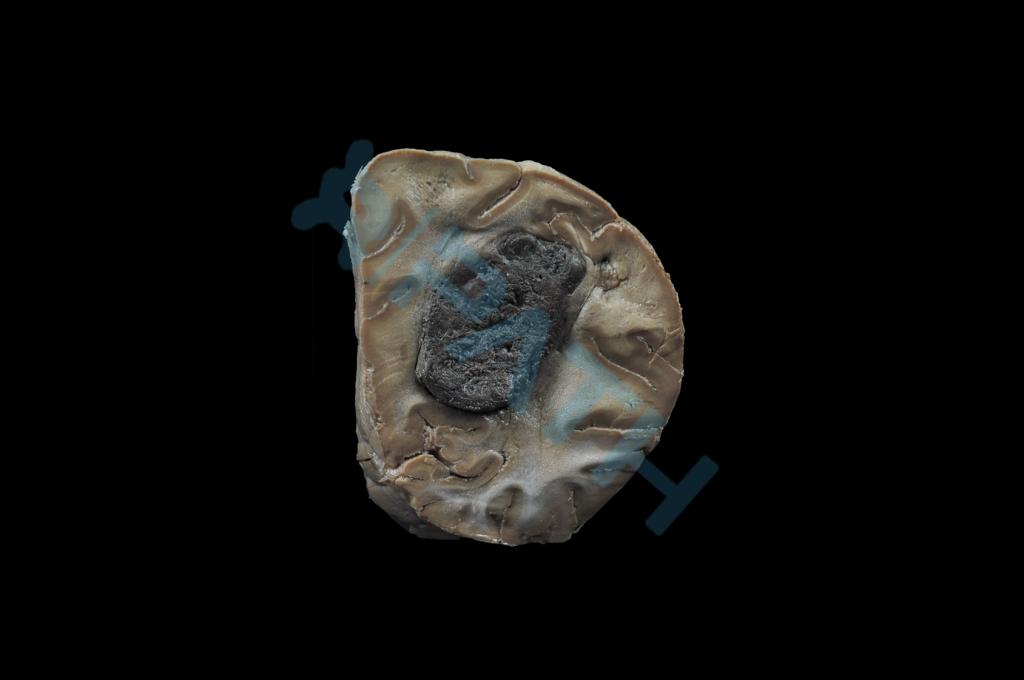

绒癌